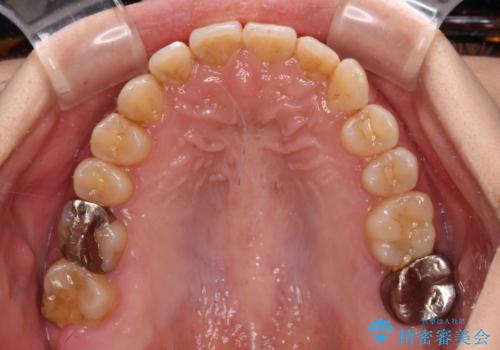

前歯のデコボコとクロスバイト インビザラインによる矯正治療

- 上下のクロスバイトと前歯のデコボコを気にして来院された患者様です。

骨格的に下顎がやや前方にあり、奥歯にクラウンが装着されているため、矯正治療後半の不安定な咬み合わせを避けるのであればワイヤー矯正がおすすめとなりますが、希望によりインビザラインにて治療を行うこととしました。

インビザラインを用い、IPR(歯と歯の間を削る)と歯列全体を拡大させることで、歯並びを整えていくこととしました。